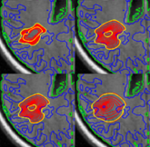

Brain Tumor Segmentation and ModelingWe are interested in developing computational methods for the assimilation of magnetic resonance image data into physiological models of glioma - the most frequent primary brain tumor - for a patient-adaptive modeling of tumor growth. More... New: Menze BH, Van Leemput K, Honkela A, Konukoglu E, Weber MA, Ayache N and Golland P. A generative approach for image-based modeling of tumor growth. Proc IPMI 2011. LNCS. 12p